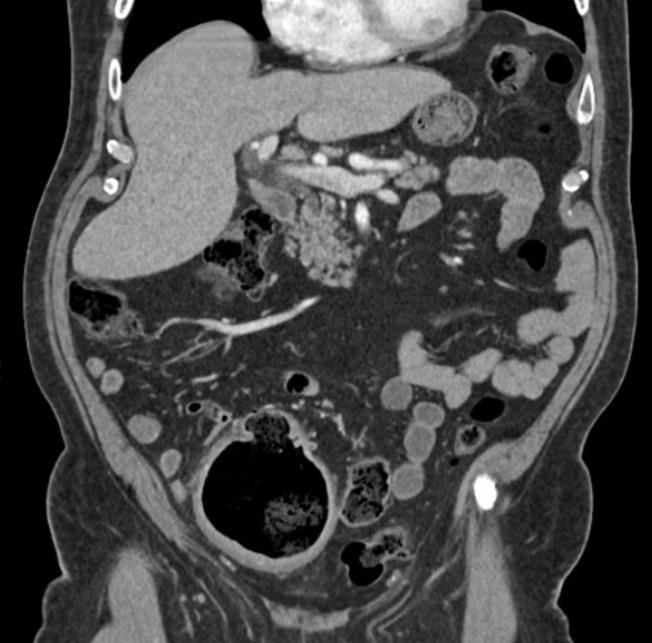

This report describes the case of a 66-year-old man who developed a giant colonic diverticulum with primary symptoms including dull and chronic pain in the right lower quadrant at presentation. The patient had undergone several computed tomography scans of the abdomen and pelvis over the previous two years, through which the natural history of this rare entity could be retrospectively observed. The patient was successfully treated with a robot-assisted sigmoid colectomy and had an uneventful recovery with resolution of symptoms during the follow-up.